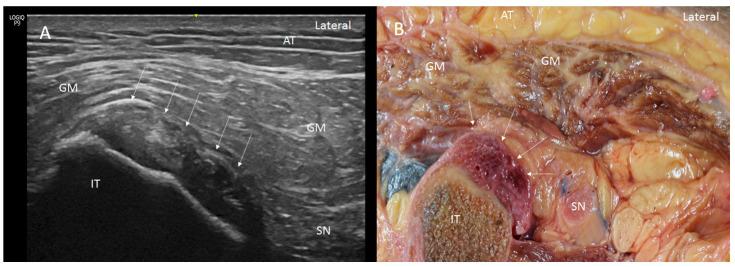

The proximal attachment of the hamstring muscles presents a hyperechogenic line surrounding the origin of the semimembranosus and the long head of the biceps femoris muscles, as well as another hyperechogenic line covering the sciatic nerve. The anatomical and histological study confirms the ultrasound results and shows different layers forming the sacrotuberous ligament. Furthermore, it shows that the proximal attachment of the semimembranosus muscle has a more proximal origin than the rest of the hamstring muscles. Moreover, this muscle shares fibers with the long head of the biceps femoris muscle and expands to the adductor magnus muscle. The histological analysis also shows the dense connective tissue of the retinaculum covering the long head of the biceps femoris and semimembranosus muscles, as well as the expansion covering the sciatic nerve.

腘绳肌近端附着点呈现一条高回声线,围绕半膜肌起点和股二头肌长头,以及另一条覆盖坐骨神经的高回声线。解剖和组织学研究证实了超声结果,并显示了构成骶结节韧带的不同层次。此外,研究表明半膜肌近端附着点的起点比其他腘绳肌更靠近近端。而且,该肌肉与股二头肌长头共享纤维,并延伸至大收肌。组织学分析还显示了覆盖股二头肌长头和半膜肌的支持带的致密结缔组织,以及覆盖坐骨神经的延伸部分。